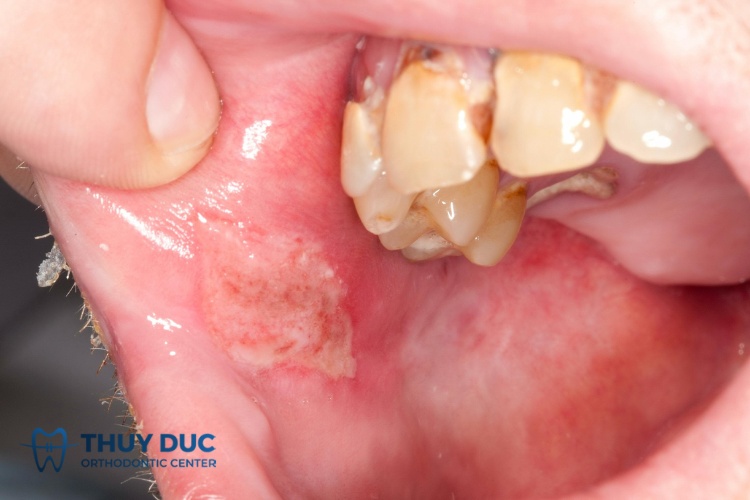

Ung thư miệng

Ung thư miệng thường xảy ra khi khoang miệng bị tổn thương tái đi tái lại nhiều lần. Tình trạng này khiến các tế bào bị biến đổi ác tính, tăng sinh quá mức và phát triển thành khối u, ổ loét. Đặc điểm của ung thư miệng gồm:

- Khoang miệng xuất hiện các vết loét, vết trợt hoặc u sùi ở vị trí bất kỳ, phổ biến là lưỡi.

- Đôi khi, các vết loét có thể nằm trên u sùi.

- Tổn thương loét là khối hỗn hợp, có màu đỏ xen lẫn trắng vàng hoặc đen do hoại tử, không có bờ rõ ràng với khu vực xung quanh.

- Quanh vết loét có thể bị chai cứng, chạm vào gây chảy máu và thường có mùi hôi khó chịu.